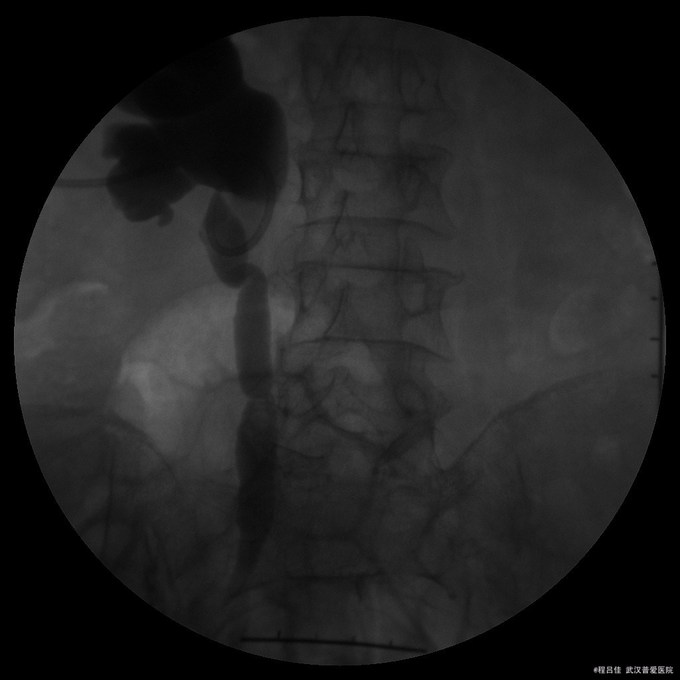

查体:腹部平坦,无胃肠型,无压痛及反跳痛,肠鸣音正常,阴道仍有粪渣样物质排出。 辅查: 膀胱镜检查:膀胱阴道瘘诊断明确 腹部CT:1.“宫颈癌行子宫全切术后+化疗后+回肠代膀胱造瘘术后+右肾造瘘术后"改变:回肠代膀胱;膀胱积气及膀胱壁增厚,膀胱后壁欠连续,并见后凸小囊腔,由于其后方阴道及直肠显示欠清楚,考虑膀胱阴道瘘可能性大,未能确定是否与直肠相通,请结合临床。 2、盆腔前腹壁下包裹性积液积气形成;腹壁切口区改变,盆腔术区肠管聚拢、结构紊乱,考虑粘连伴小肠低位不完全性机械性肠梗阻。 3.胆囊多发结石,肝S6囊肿,右肝内胆管轻度扩张。

诊断:1.小肠阴道瘘,2.小肠不完全性肠梗阻,3.放射性膀胱炎,4.放射性直肠炎,5.尿路感染,6.宫颈癌子宫切除术后,7.双下肢静脉血栓 治疗:在全麻下行回肠代膀胱术,术后12天患者排便时阴道内有大便流出,肠道造影未见明显瘘口,多次请胃肠外科、妇产科、消化内科等相关科室会诊,考虑盆腔段小肠因放射性肠炎术后出现肠瘘,入院经完善相关检查,予以抗感染、补液、加强营养支持、克赛抗凝等对症治疗。